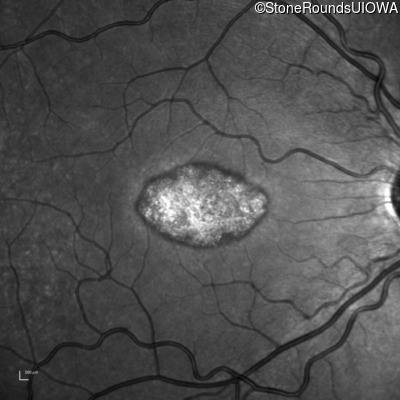

This 22 year old man had macular abnormalities noted incidentally at a routine eye exam at age 19. Since then, he has experienced a gradual loss of acuity particularly in the left eye.